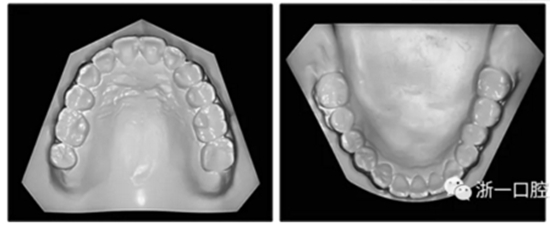

圖3. 治療后面部和口內(nèi)照片

圖4. 治療后研究模型